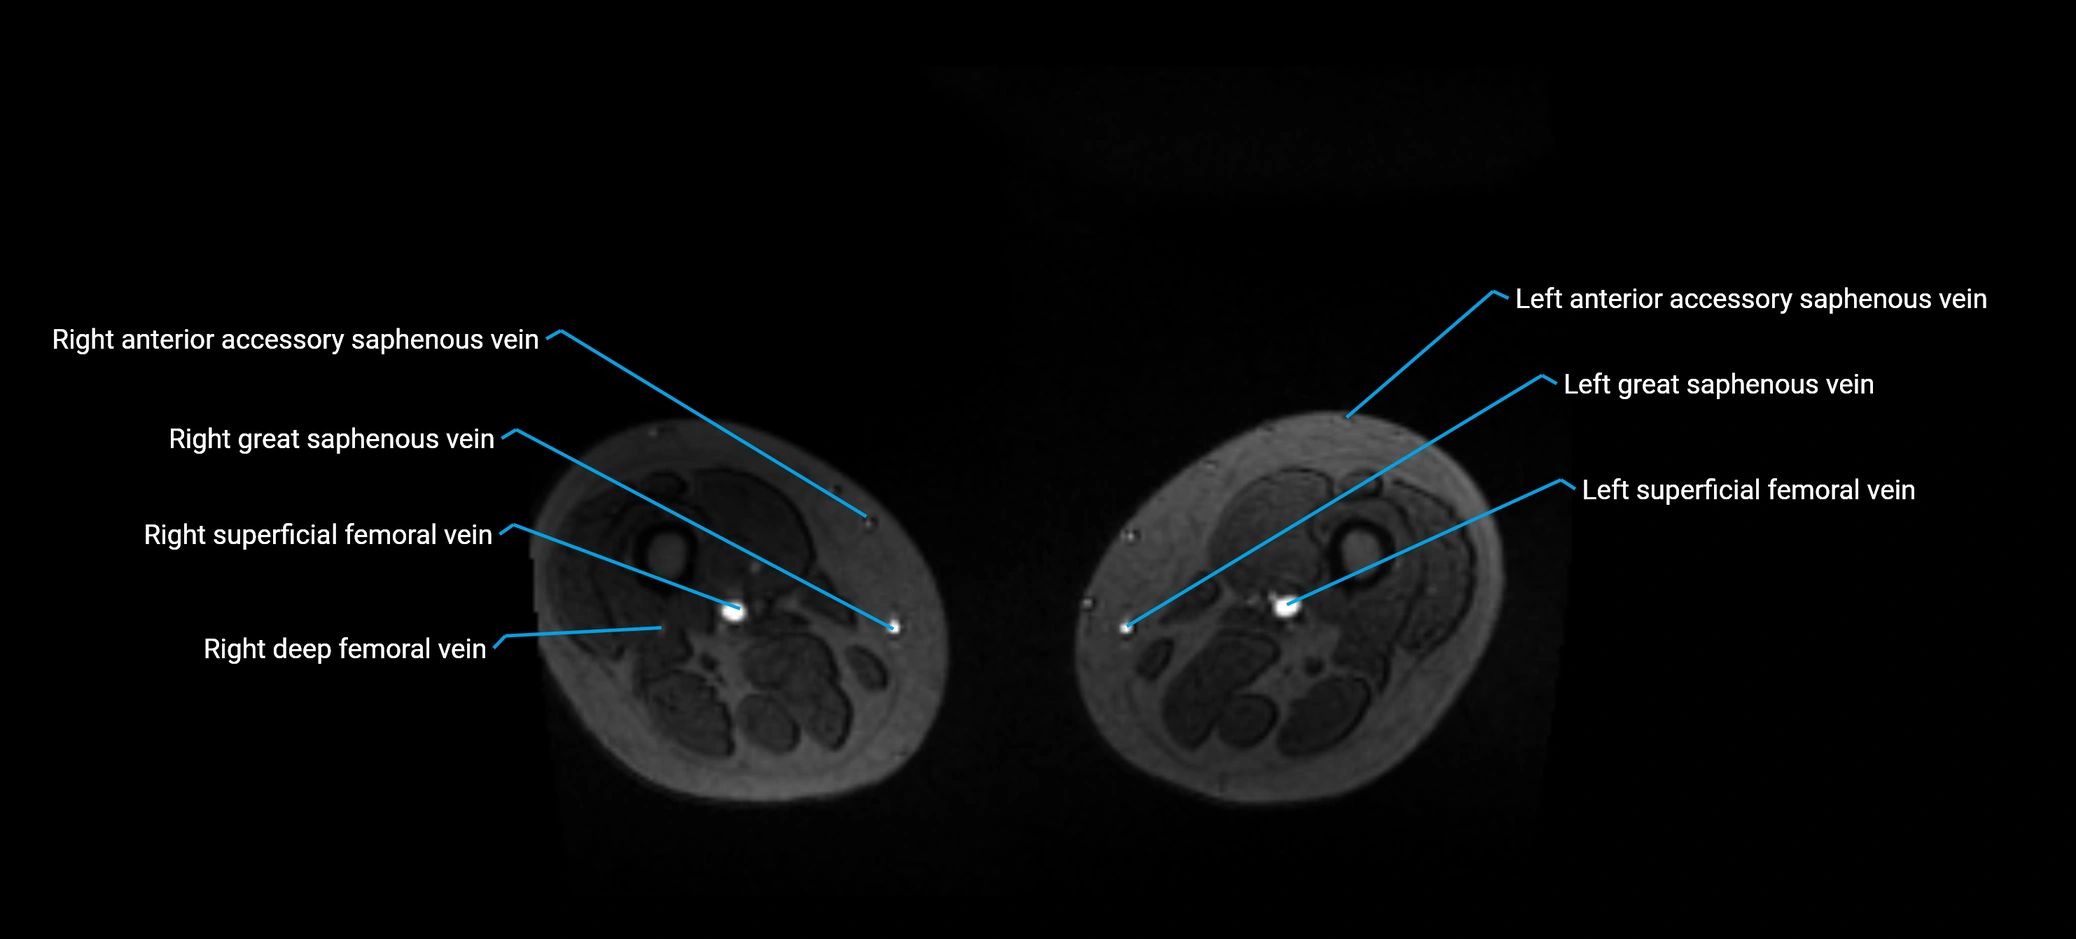

image